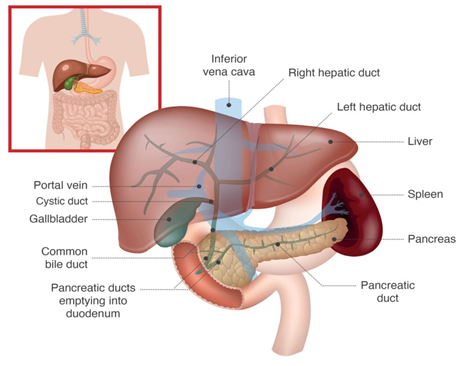

Het galwegsysteem verder uitgelegd

Het galwegsysteem bestaat uit een netwerk, of ook wel boom-achtige structuur, van galwegen in de lever en de hoofdgalweg (common bile duct, CBD) buiten de lever.

In de lever zitten smallere galwegen, vergelijkbaar met hele kleine bloedvaatjes. Zij voeren gal af vanuit de levercellen naar de steeds groter wordende galwegtakken. De rechter en linker galwegtakken in de lever verzamelen de gal en komen samen buiten de lever en vormen samen de grote galweg (CBD). Deze galweg voert de gal naar de galblaas en naar de 12-vingerige darm.

De galblaas fungeert als een reservoir voor de gal totdat eten in de 12-vingerige darm komt. Het is met een kleine galwegtak verbonden aan de hoofdgalweg, op ongeveer 1/3 van de bovenkant van de hoofdgalweg (de ductus cysticus).

Figuur 3: Het galweg systeem.

Illustratie: AMMF 2022 ©